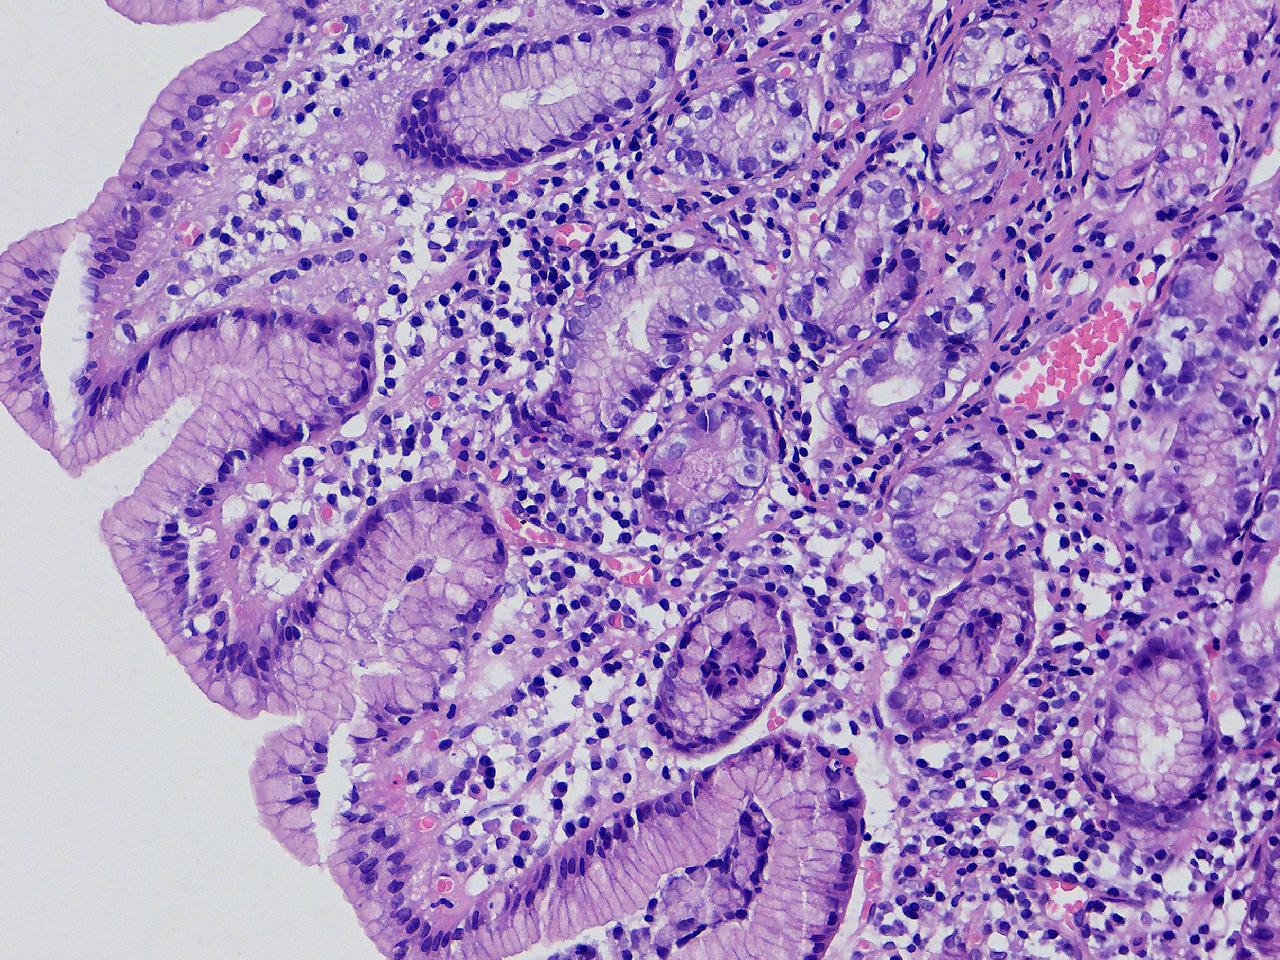

间质内是炎细胞吗?

男,49岁,胃镜活检,胃窦粘膜红白相间,以红为主,后壁见一直径约0.4cm大小片平隆起,表面糜烂,活检1块送检,质软弹性可。

胃窦活检

灰白色不整形软组织1块,直径0.2厘米。

是!还有组织细胞

幽门型粘膜中度慢性炎

是的,主要是淋巴细胞和浆细胞。